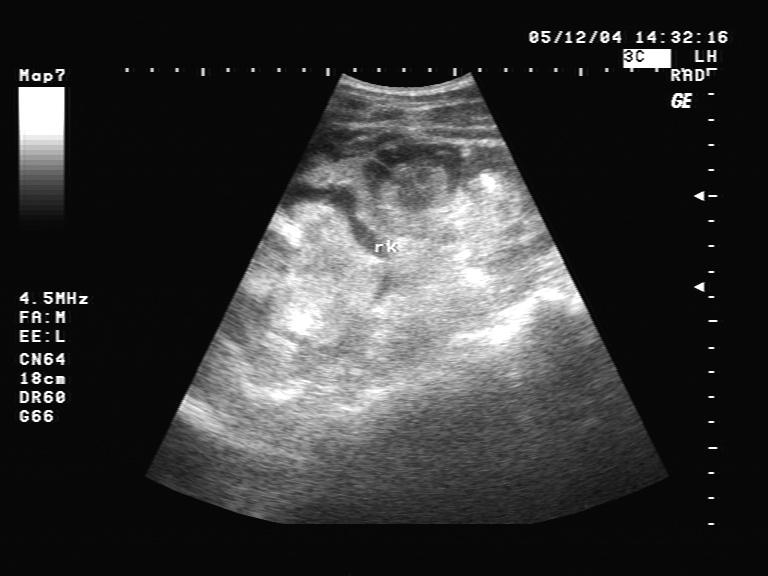

右肾挫裂伤 - 超声医学讨论版 - 爱爱医医学论坛

图片尺寸442x320